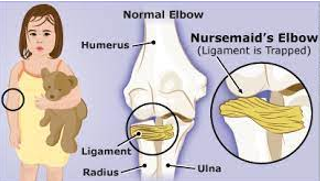

Radial Head Subluxation “Nursemaid’s Elbow”

Cause:

Caused by a pulling motion on the arm that stretches or tears the annular ligament surrounding the radial head, displacing the radial head.

Typically occurs in children under 5 years of age.

Injury Reduction Technique:

The elbow is flexed to 90 degrees, and then the forearm is fully and firmly supinated.

Clinical Manifestations:

Holds the affected arm close to the body.

Pain with forearm supination is always present.

No obvious deformity, PNV (peripheral neurovascular) compromise, bony tenderness, or swelling.

History of the arm being pulled.

The ligament becomes entrapped within the joint, preventing spontaneous reduction.

Nursing Measures:

Provide education and reassurance for the child and parents.

May need to assist with the reduction.

Administer pain medication as needed.